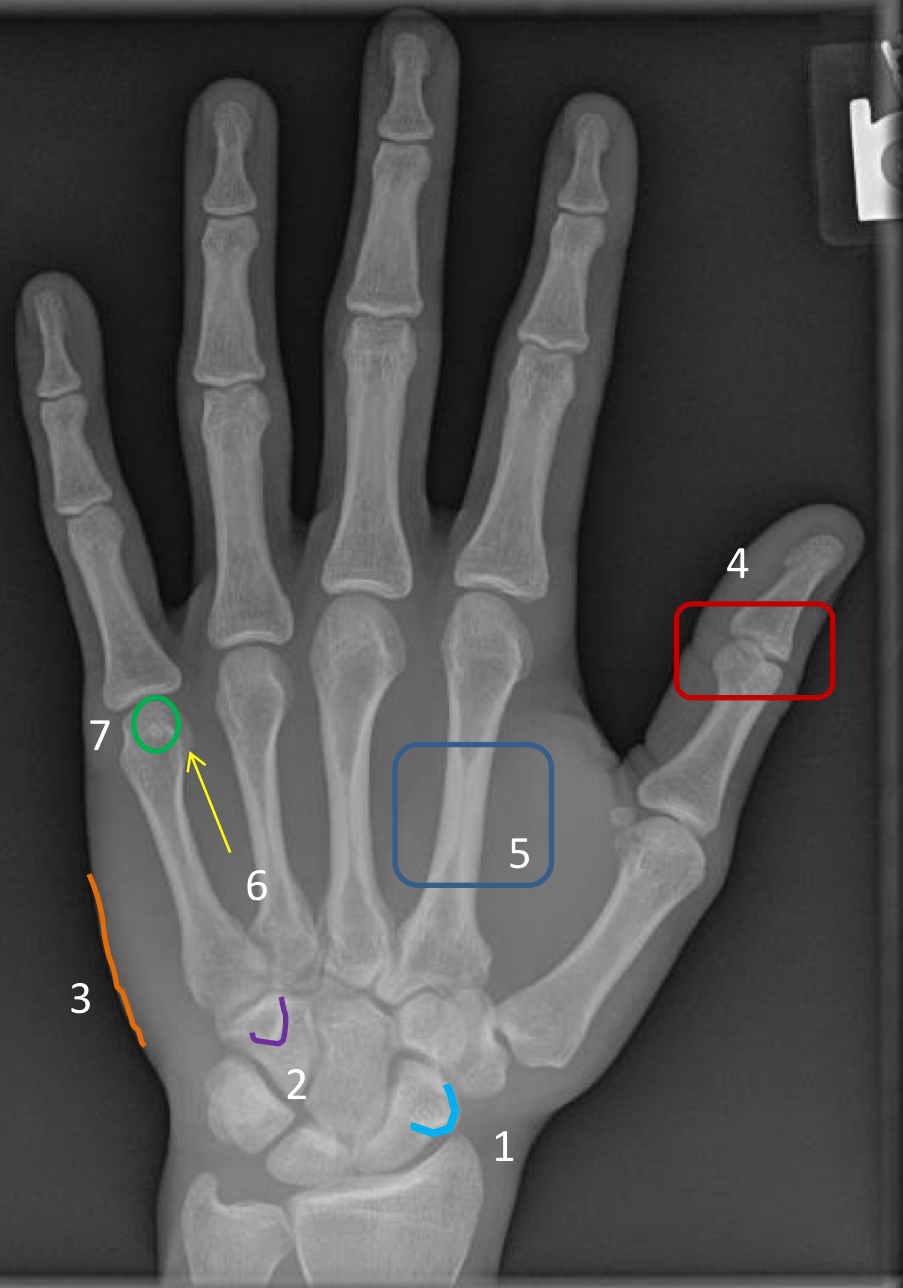

What view is this?

medial oblique

1?

scaphoid tubercle

2?

hook of hamate

3?

hypothenar eminence

4?

1st interphalangeal joint (poorly visualized)

5?

2nd metacarpal diaphysis

6?

“condylar” appearance at the head of metacarpal